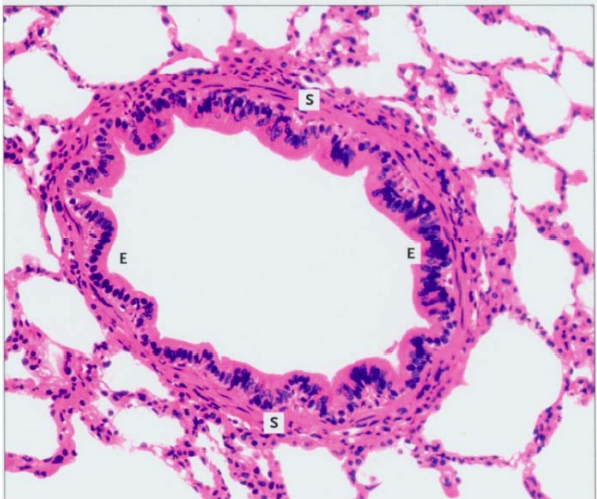

What are the layers of the trachea?

What comprises the tracheal mucosa?

respiratory epithelium and lamina propria

What comprises the tracheal submucosa?

connective tissue and glands (serous and mucous)